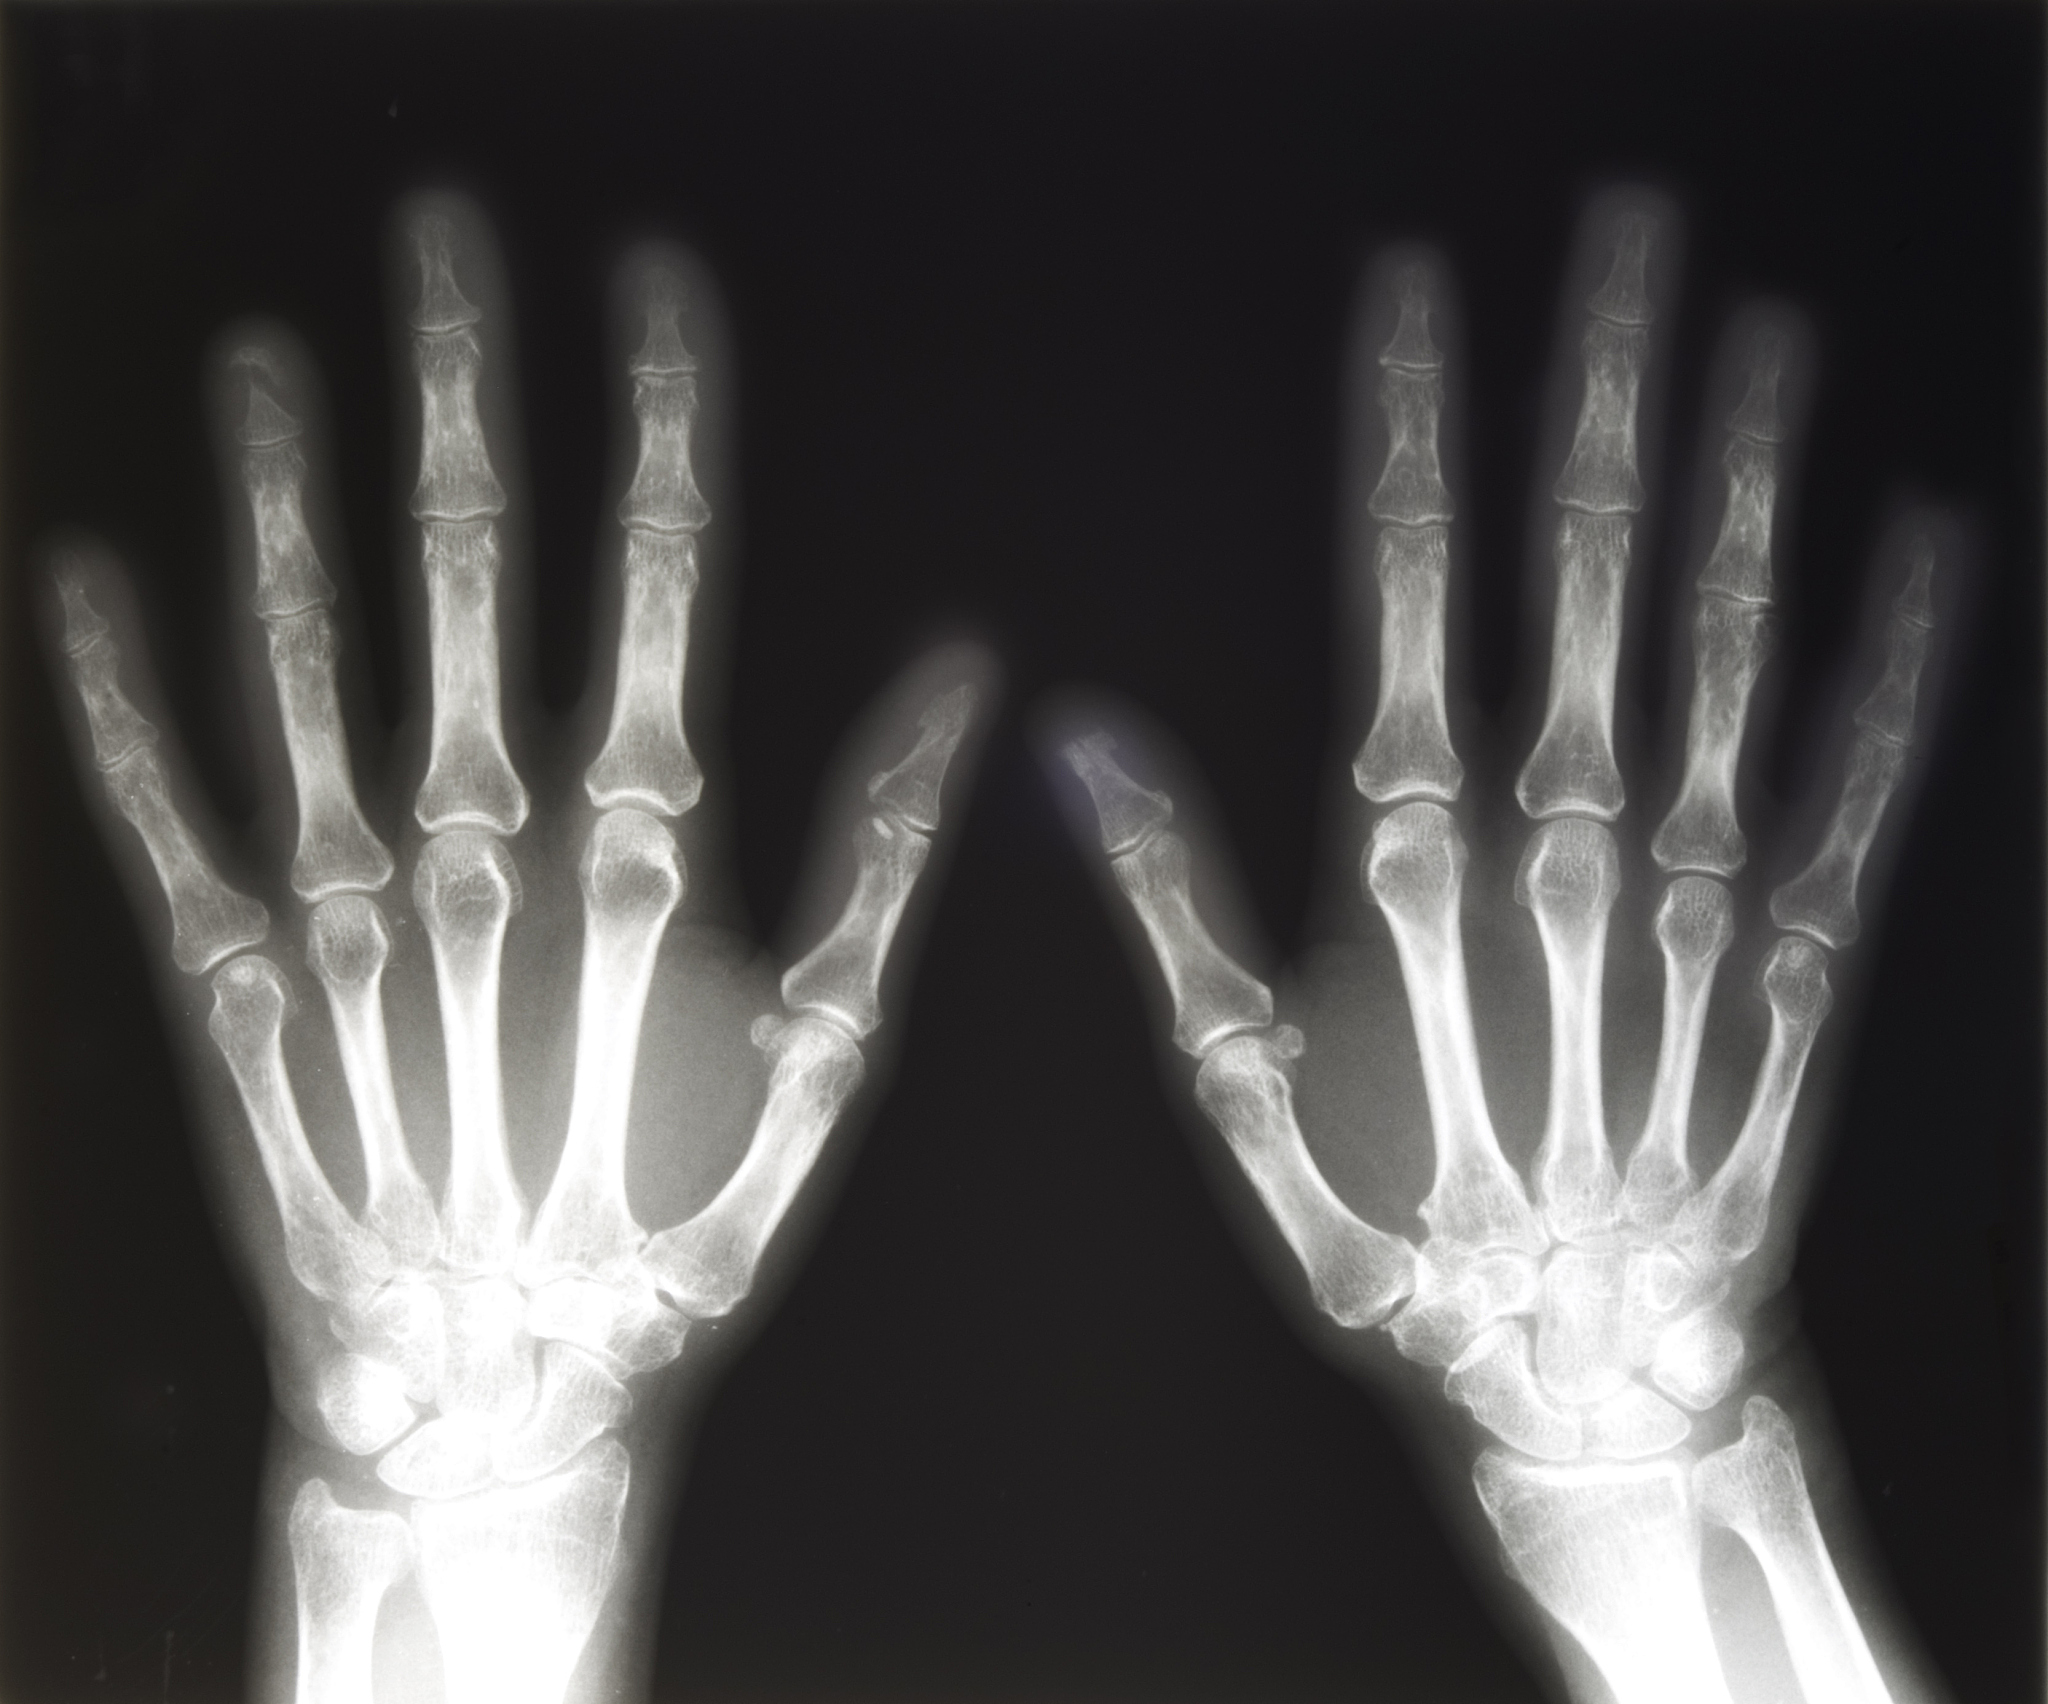

'X线拍片法'是通过对儿童的手腕、手掌、膝盖等部位进行X线拍片,然后根据骨骼发育情况来判断其骨龄。这种方法主要依赖医生的经验和专业知识,需要通过对多个部位的不同角度的拍片进行分析。